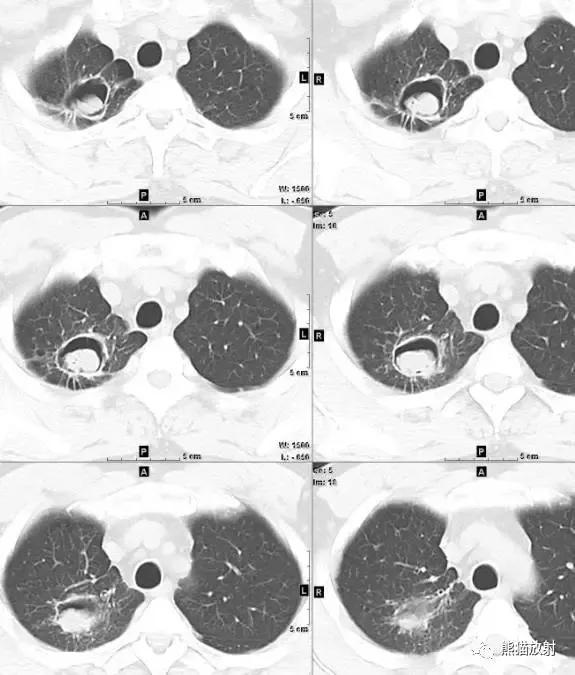

肺空洞是一种常见的疾病,它在肺部形成了一个孔洞。这个孔洞通常由于感染引起的肺组织坏死而形成。最常见的原因是结核菌感染,但也可能与其他细菌、真菌或寄生虫感染有关。当感染侵袭肺部时,免疫系统会试图清除感染,但有时会导致肺组织死亡,并形成空洞。

肺空洞的症状各异,包括持续咳嗽、咳出血痰、胸痛以及呼吸困难。然而,有些人可能没有任何明显的症状。要确诊肺空洞,医生通常会进行一系列检查,包括胸部X射线、CT扫描和支气管镜检查。这些检查可以帮助医生确定肺部是否存在空洞,并排除其他可能的疾病。